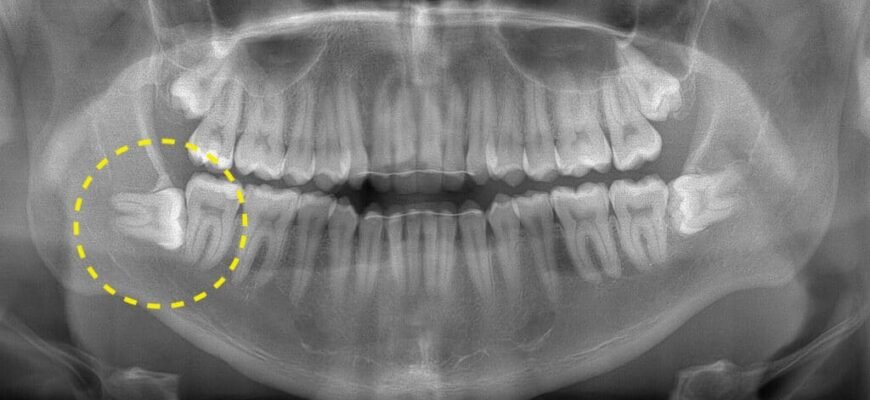

В скільки років ростуть зуби мудрості? — Детальна Інформація Зуби мудрості… Ці підступні “гості”, які вміють з’явитися у найнеочікуваніший момент.